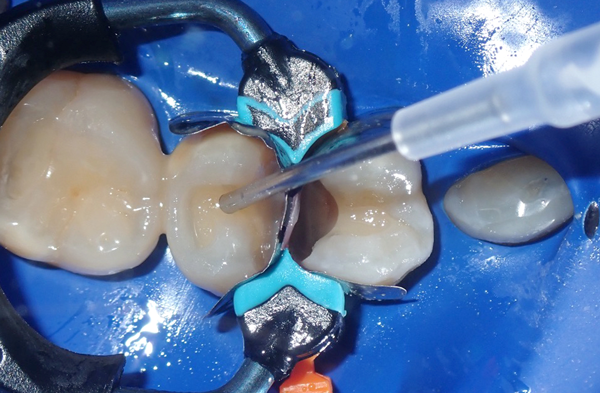

In this case, both teeth were prepped, and the Quad System was placed to ensure stable contact creation during the restoration process. Anatomically shaped wedges and separating rings were inserted to achieve optimal band adaptation and gingival seal (Fig. 5 & 6).

FIG. 5

FIG. 6

Simultaneous placement facilitates the restoration of back-to-back

Class II lesions with proper contact and contour.